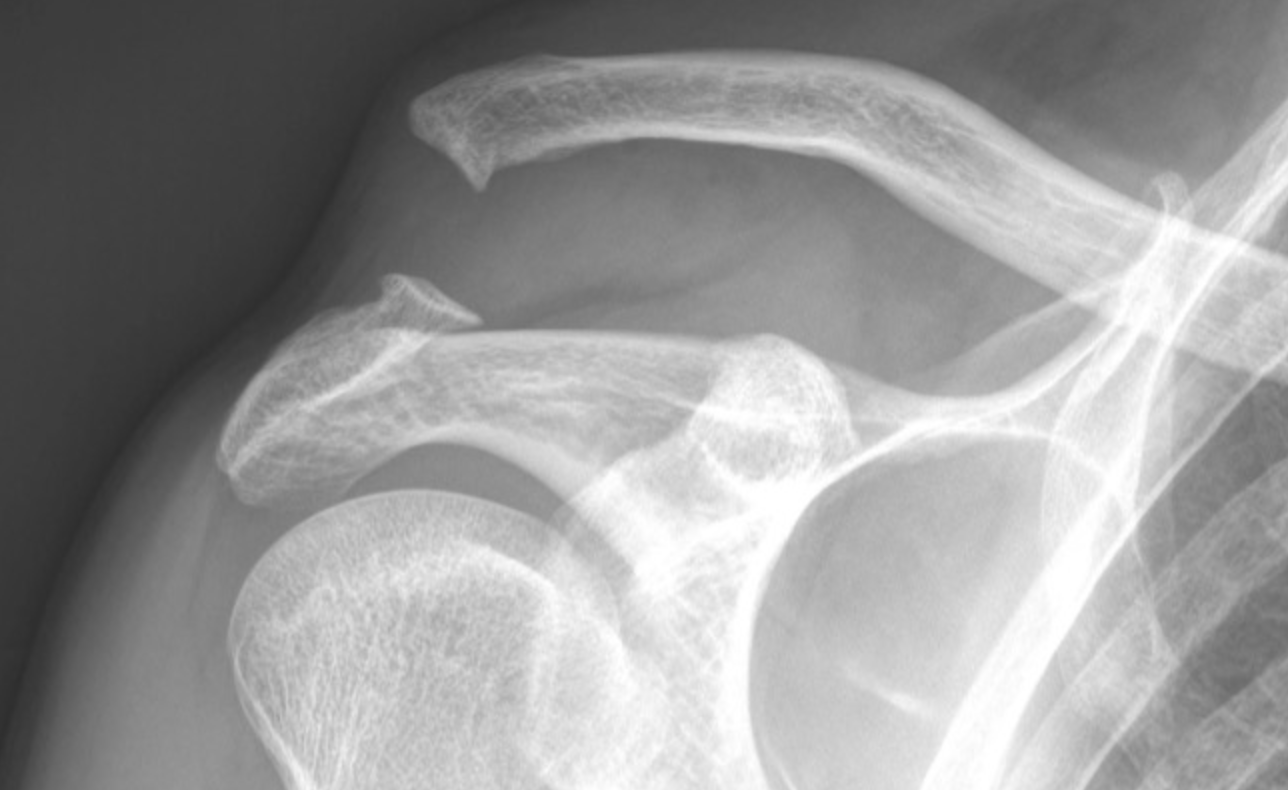

Acromio-Clavicular Dislocation

It occurs when the ligaments connecting the collarbone (clavicle) to the acromion of the shoulder blade are damaged, usually due to a direct blow to the shoulder or a fall onto an outstretched arm.

X-ray image of a shoulder joint showing broken clavicle and fractured humerus.